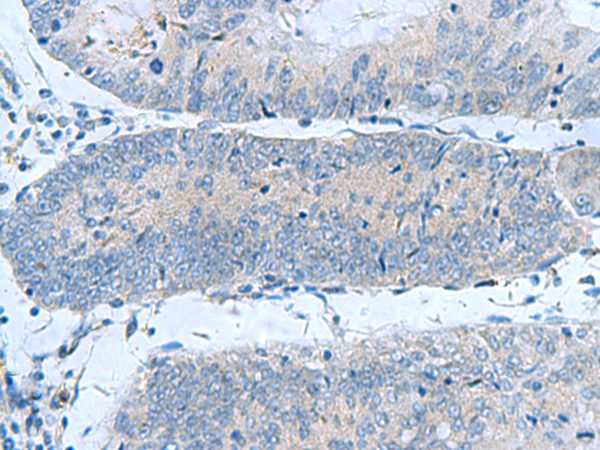

IHC (Immunohistochemistry)

(The image is immunohistochemistry of paraffin-embedded Human liver cancer tissue using (GUCA1A Antibody) at dilution 1/50.)